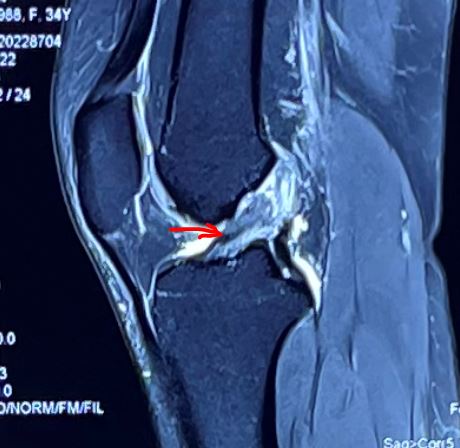

图 前交叉韧带断裂 可见残端

膝关节扭伤后可以通过核磁MRI清晰显示前交叉韧带损伤,但韧带残端可见